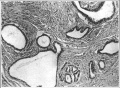

卵巢炎